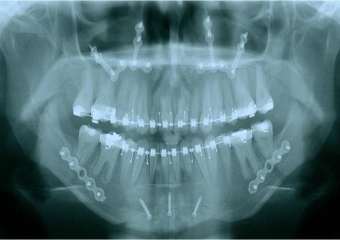

Rx inicial - Clínica Cliniface

Rx inicial